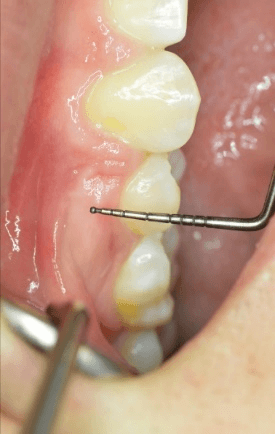

Measurements were made in the x, y, and z planes to determine gingival cleft severity. Figure 4 demonstrates a gingival cleft between the upper right second premolar and canine with the periodontal probe just outside of the cleft. Figure 5 Illustrates the same site with the periodontal probe inside the cleft in the Z direction (occlusal-gingival). Figure 6 Illustrates probing depth of the gingival cleft in the Y direction (bucco-lingual).

Figure 4: Gingival cleft next to periodontal probe.